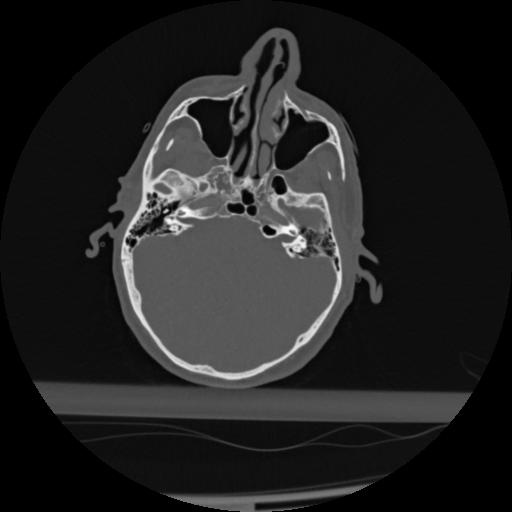

22 ANGIO,CE,Vol,0.5,ANGIO,,